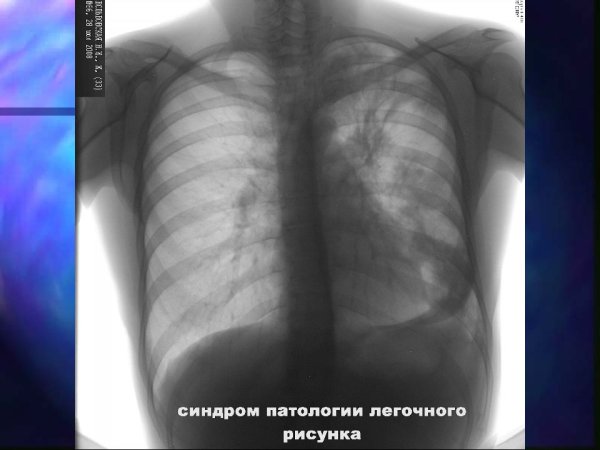

Синдром патологии легочного рисунка

Патология легочного рисунка - это состояние, при котором обнаруживается изменение образца распределения сосудистых и бронхиальных структур в легких. Это может быть вызвано различными причинами, такими как хронические заболевания легких, врожденные аномалии или инфекционные процессы. При патологии легочного рисунка могут наблюдаться различные изменения на рентгенограммах, такие как утолщение сосудов, усиление бронхиального образца или появление тени. Диагностика и лечение этого состояния требуют комплексного подхода, основанного на клинических данных и дополнительных исследованиях. Целью такого лечения является устранение основной причины патологии легочного рисунка и восстановление нормальной структуры и функции легких.